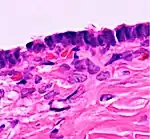

Histopathology

In case an ovarian cyst is surgically removed, a more definite diagnosis can be made by histopathology:

| Type | Subtype | Typical microscopy findings | Image |

|---|---|---|---|

| Functional cyst | Follicular cyst |

|

| Cystadenoma | Serous cystadenoma | Cyst lining consisting of a simple epithelium, whose cells may be either:[19]